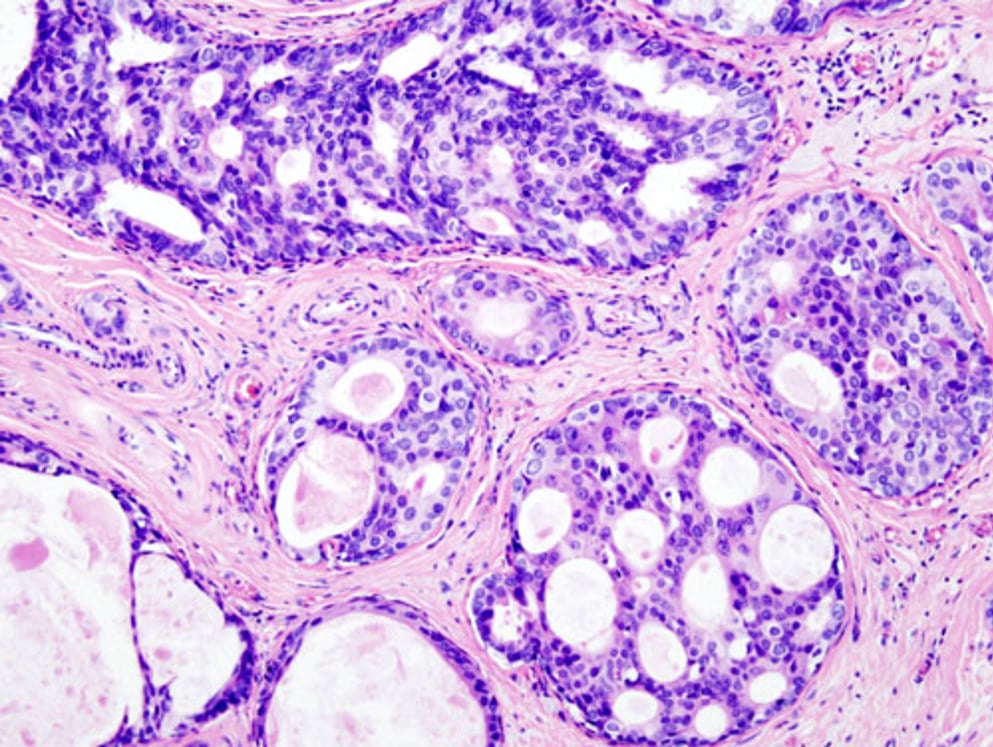

Исследование: микропрепарат молочной железы в медицине

Раздел: Снимки-откровения